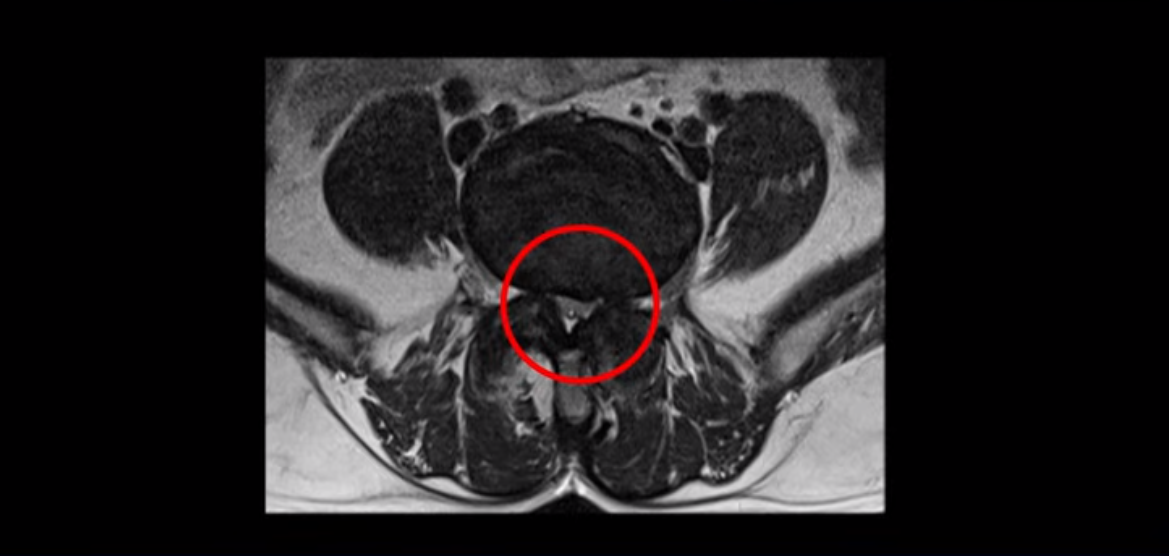

이분은 허리 다섯 마디 중 4번 5번, 5번 1번에 감압술로 눌린 신경을 풀어주는 수술을 받았습니다.

후관절을 떼어낸 흔적이 보입니다.

단면으로 보면 왼쪽 후궁을 제거한 흔적이 보입니다.

5번 1번도 왼쪽 후궁을 열고 수술 받았습니다.

하지만 중심성 협착은 여전히 심한 상태입니다.

이분은 오른쪽, 왼쪽 다리에 모두 방사통이 심하고 왼쪽 다리에 마비 증상, 즉 풋드랍(족하수) 증상이 있습니다. 왼쪽 신경 가지가 빠져나가는 추간공을 보면 두 마디가 좁아져 있습니다.

이런 신경 구멍이 좁아져 있는 걸 협착이라고 합니다.